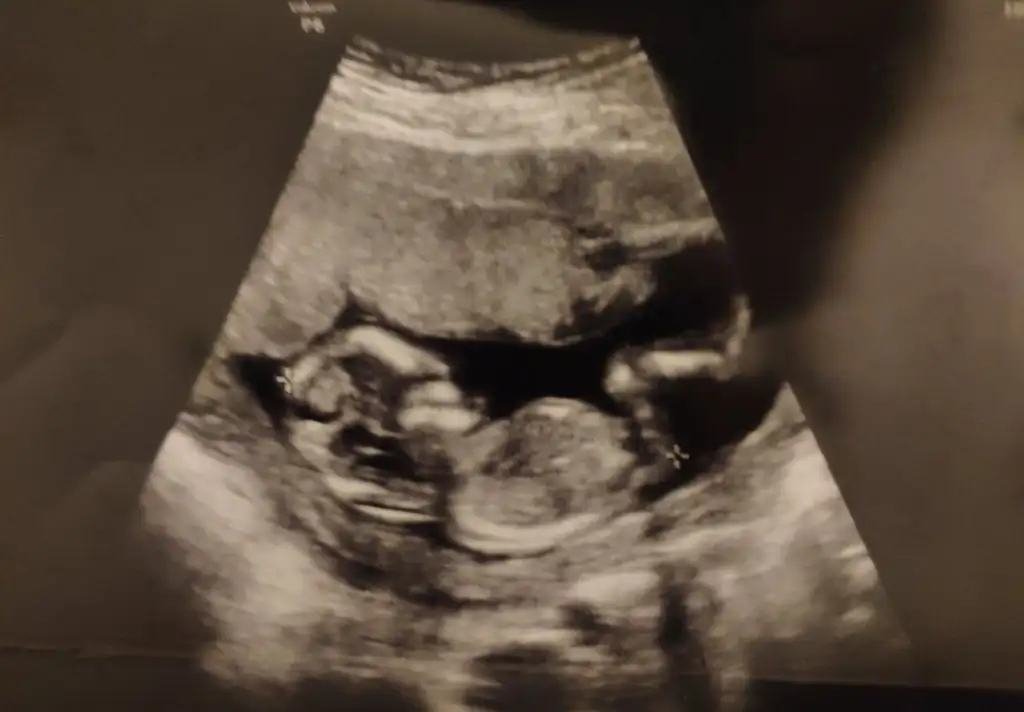

Kızlar cinsiyeti erkek mıdır ?

IMG-20190430-WA0015.webp